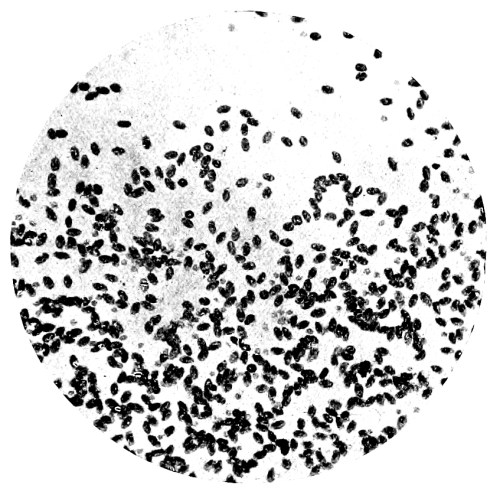

| 8. | Measurement of Blood Corpuscles (human) | 97 |

| 9. | Measurement of Blood Corpuscles (sheep) | 97 |